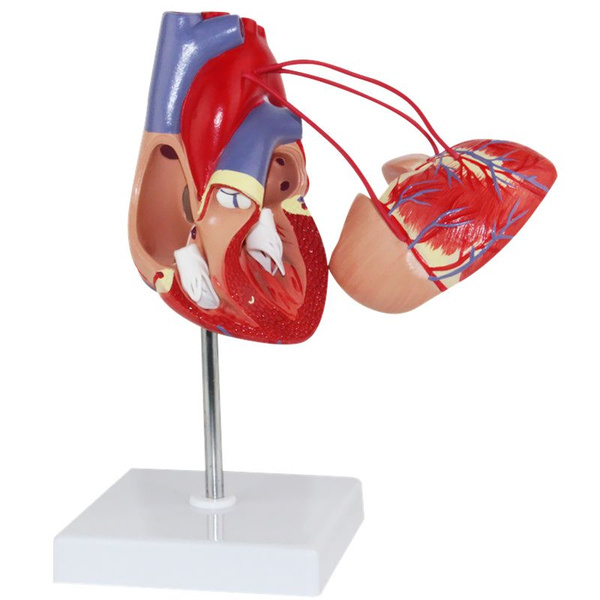

Фотографии и 3D-модели анатомии сердца человека